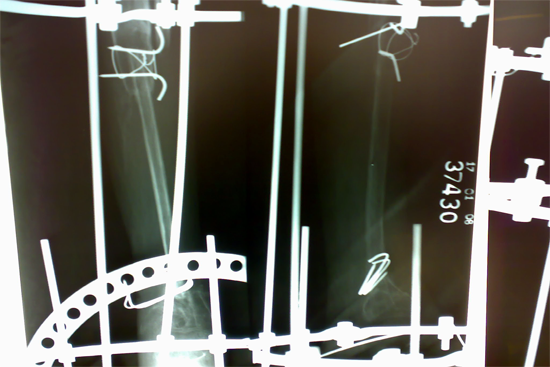

Tibialisation of Fibula

Method

We have done Huntington technique by stage ilizarov procedure. Here is the diagrammatic representation of our method.